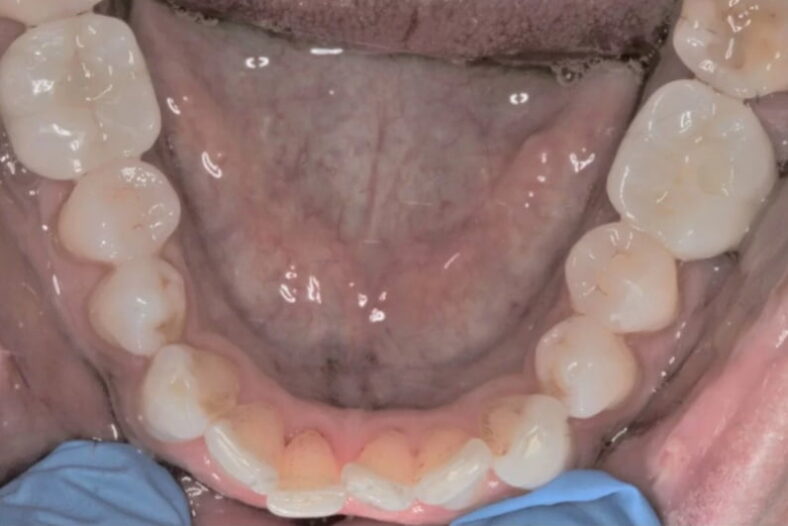

This patient lost his two of his lower molar teeth. Implants were placed on either side to replace…